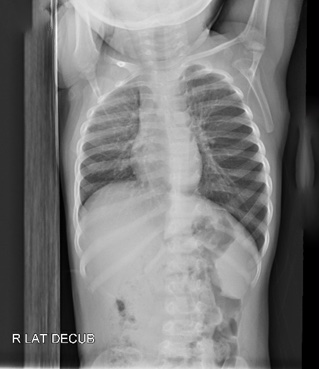

Answer: Non-radiopaque foreign body in left airway beyond the carina with hyper lucency of the left lung consistent with air trapping

- Air trapping seen on all views

- normally with decubitus xrays dependent lung collapses slightly, which is seen here on the right but not on the left

- patient taken to the OR with ENT and peanut was removed via bronchoscope from the left main stem bronchus, she was discharged the following day